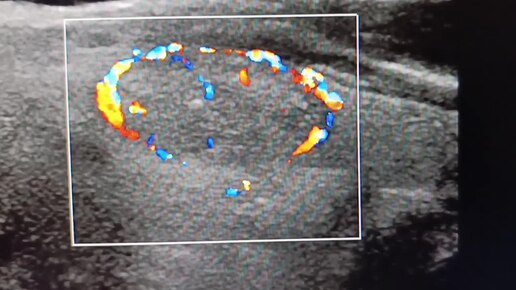

Начинающим врачам УЗИ: узел щитовидной железы в ЦДК.